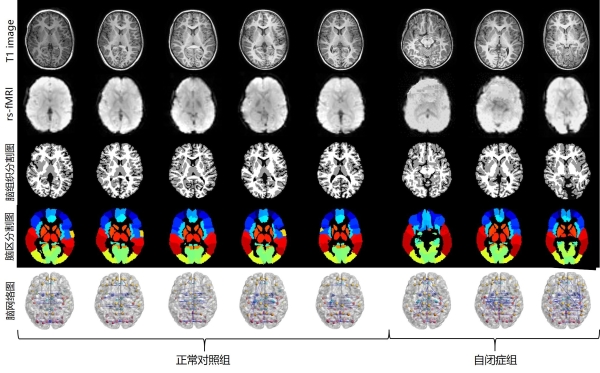

• 苏州医工所在脑疾病辅助诊断研究方面取得进展

脑 特征 方法

2022-09-26 17:00